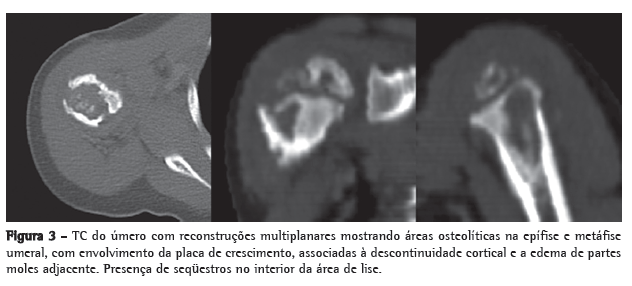

Os exames subsidiários mostraram hemograma com 8.200 leucócitos (9 bastões e 66 neutrófilos); velocidade de hemossedimentação de 32 mm na primeira hora, proteína C reativa < 6,0 mg/L; sedimento urinário normal; radiografia de tórax normal; e PPD positivo reator forte, com 18 mm. A TC de úmero mostrou múltiplas lesões líticas na região proximal do úmero, envolvendo a epífise, a metáfise e a diáfise proximal, com descontinuidade cortical e edema de tecidos moles adjacentes (Figura 3).

Lesões líticas e escleróticas ósseas com reação periosteal caracterizam as lesões radiográficas. Os achados de TC na epífise, na metáfise e na diáfise foram consistentes com a descrição prévia em pacientes jovens.

Crianças mais velhas geralmente apresentam apenas alterações metafisárias.(4)